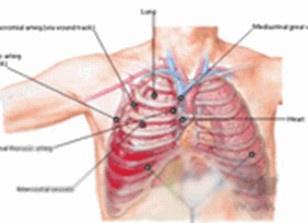

胸腔内包含有维持生命功能的两大重要器官:心脏和肺脏。正常的胸部结构和功能,对维持正常的循环、呼吸生理功能极其重要。一旦胸部受到严重损伤时,必然会影响正常呼吸、循环功能的维持,引起一系列的病理生理改变,导致呼吸循环功能紊乱甚至衰竭。若没有及时正确的处理,后果极为严重,伤员可很快死亡。在急救处理时,按病情的轻重缓急,迅速果断地采取积极有效的措施,多数伤员均可解除危险而获得治好,仅有10%的伤员需作开胸探查手术治疗。